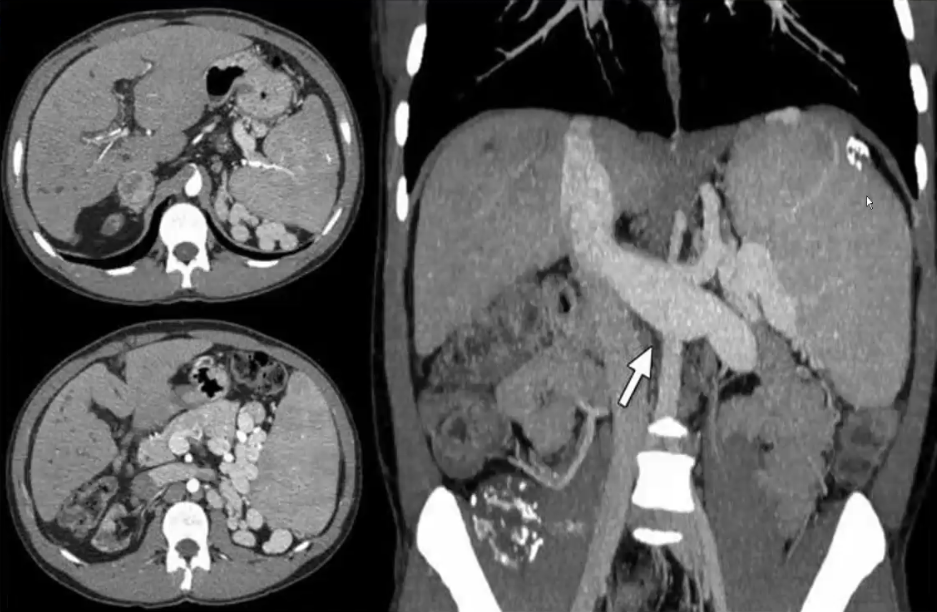

❖ CT:可见肝内出现多发囊状或柱状低密度影,可呈分支样扩张且与胆管相通

中心点征:囊状扩张的胆管内见小圆点状软组织密度影,增强后明显强化,可在偏侧,是扩张的胆管包绕点状门脉断面

蝌蚪征或囊尾征:囊状扩张的胆管与细小的胆管相通,形似蝌蚪